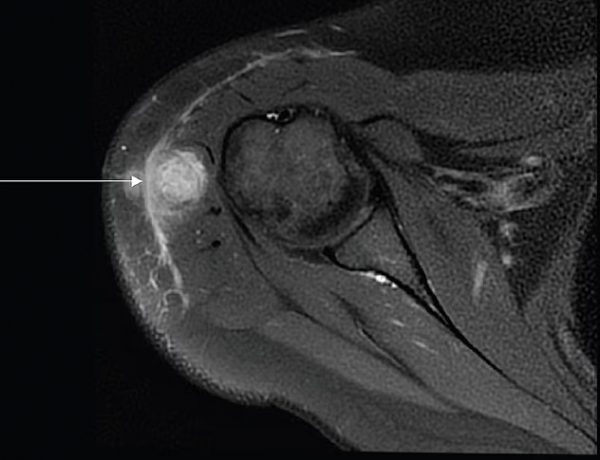

Zdrava 30-letna bolnica je pomotoma prejela cepivo proti tuberkulozi, kar je povzročilo okužbo celega telesa in s tekočino napolnjen absces v deltoidni mišici, označen s puščico. Zdravniki so oteklino sprva pripisali vnetemu kožnemu tkivu, vendar so preiskave kasneje potrdile bakterije, ki povzročajo tuberkulozo v njenem telesu.